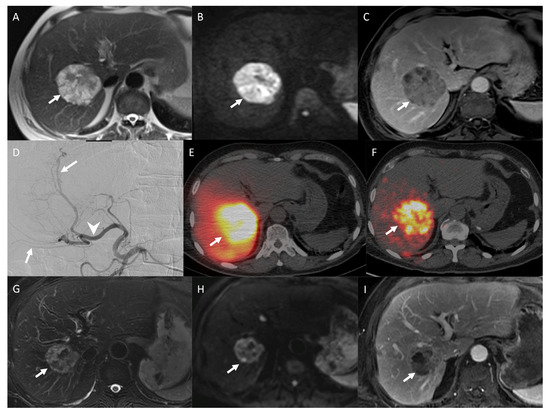

2.8.4. Pre- and Post-Treatment Imaging Prognostic Factors

3.6.2. Post-Therapeutic Imaging Prognosis Factors